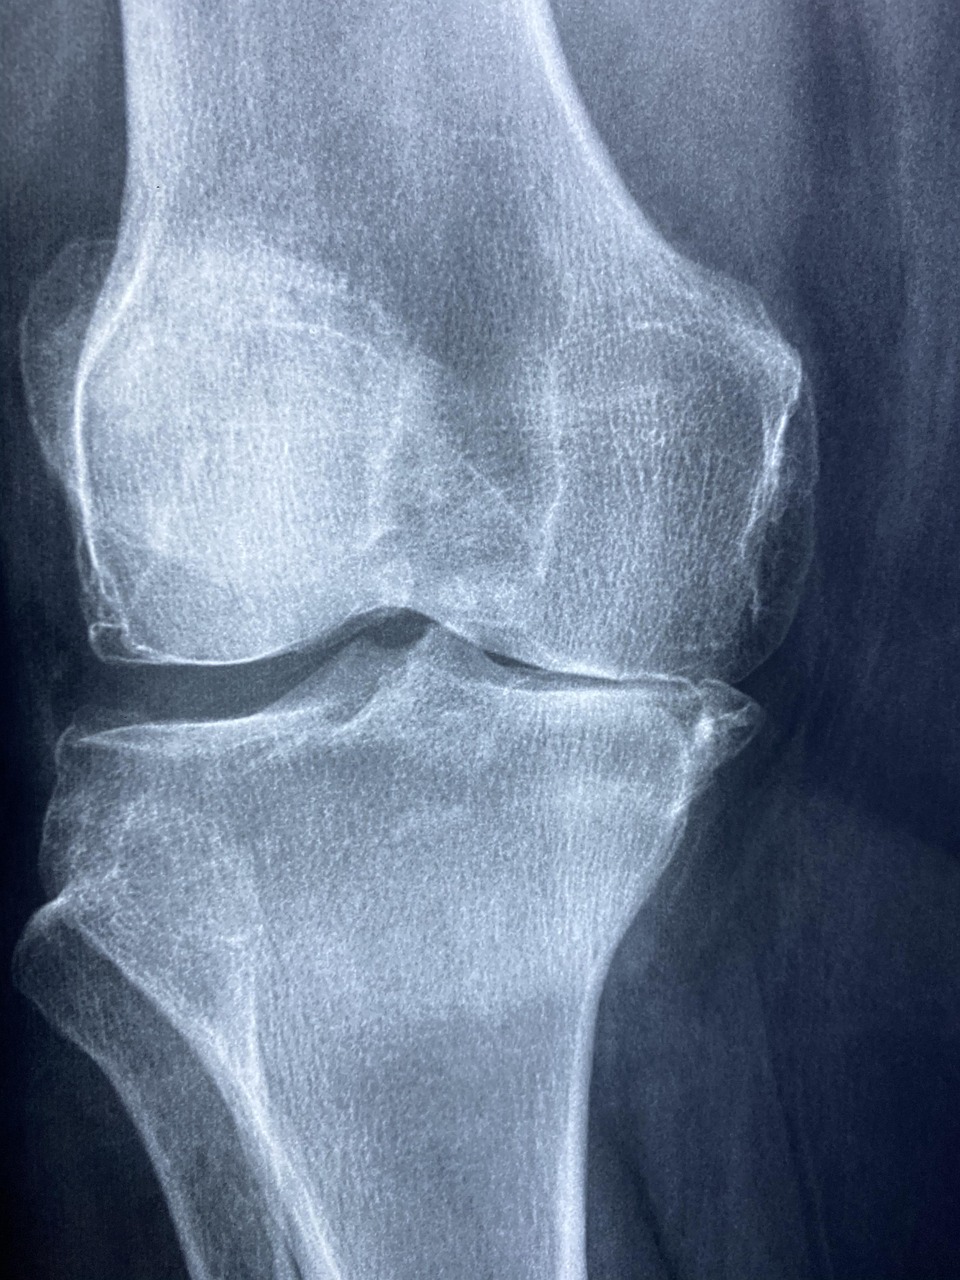

Arthrose oder Gelenkverschleiß ist eine häufige Erkrankung, die durch den Verlust von Knorpelgewebe in den Gelenken gekennzeichnet ist. Dabei kann jedes Gelenk betroffen sein, insbesondere jedoch die Knie, Hüften und Hände. Die Symptome äußern sich typischerweise in Schmerzen, Entzündungsreaktionen und Bewegungseinschränkungen. Die Schwere der Beschwerden kann von Patient zu Patient erheblich variieren; oft schreitet die Arthrose langsam voran und verursacht nur gelegentlich Probleme. In einigen Fällen können aber die Symptome rasch zunehmen und die Lebensqualität der Betroffenen erheblich beeinträchtigen.

Arthrose: die Fakten auf einen Blick

Arthrose ist eine häufige Gelenkerkrankung, die durch Gelenkverschleiß infolge von Knorpelverlust charakterisiert ist. Diese Krankheit kann jedes Gelenk betreffen, am häufigsten jedoch Knie, Hüfte und Hände. Die Symptome beinhalten Schmerzen, Entzündungsreaktionen und Bewegungseinschränkungen, wobei der Verlauf der Beschwerden stark variieren kann. Oft schreitet die Arthrose langsam voran und verursacht nur gelegentlich Beschwerden, in einigen Fällen können die Symptome jedoch schneller intensiver werden.